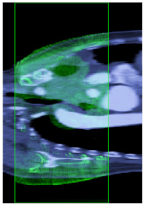

| Registration Method | Intensity Based (Single Image) | Intensity Based (The Sequence) | MI Based (No HQCS) | MI Base (HQCS) |

|---|---|---|---|---|

| Result Ground Truth: (CT_15, CBCT_60) | (CT_16.7, CBCT_60) | (CT_14.26, CBCT_60) | (CT_15.76, CBCT_60) | (CT_15.05, CBCT_60) |

| Visualization | ![]() | ![]() | ![]() | ![]() |